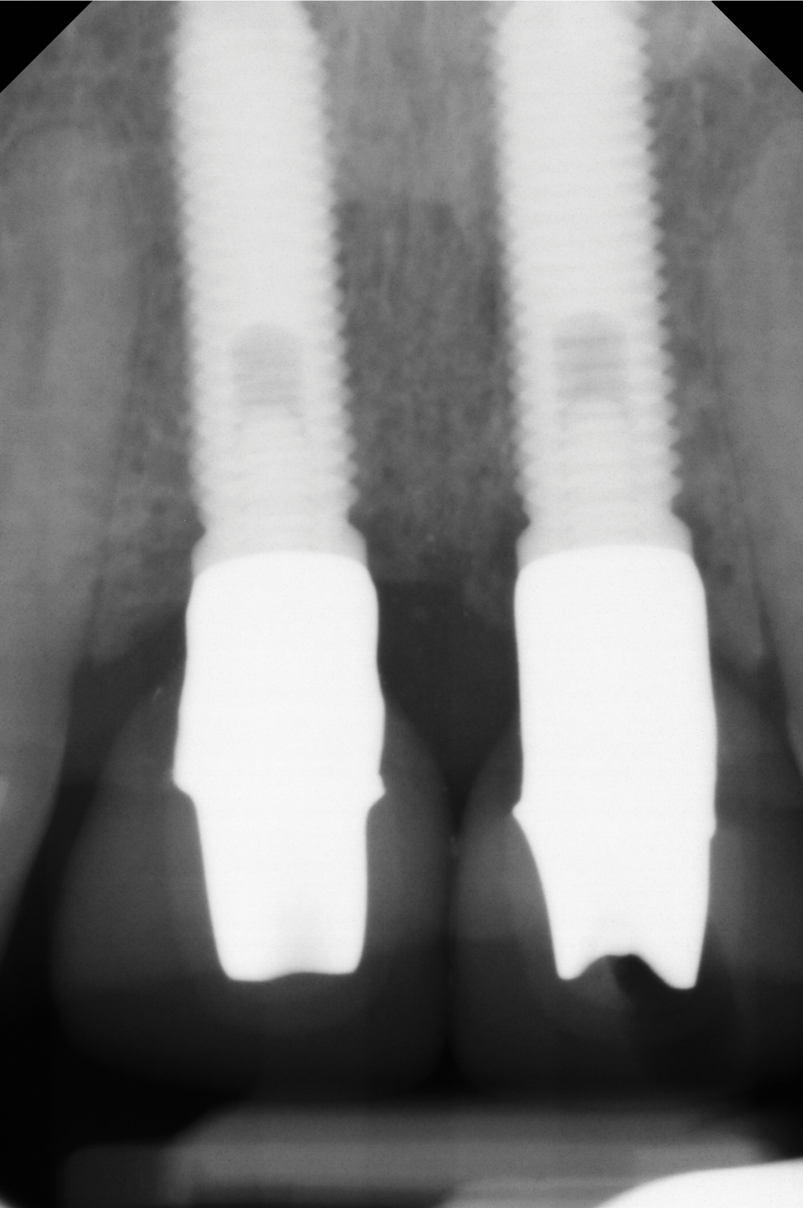

A 46-year-old systemically and periodontally healthy woman presented to the Graduate Periodontics Clinic at the University of Michigan School of Dentistry with the chief complaint of poor esthetics of her smile due to two dental implants (Nos. 8 and 9) showing their metal components (Figure 1). The patient reported that the implants had been placed 15 to 20 years previously after an accident. Clinical examination revealed that the implants had probing depths within 3 mm (facial probing depth of 3-2-3 mm for implant No. 8 and 2-2-2 mm for implant No. 9), no bleeding on probing, and no suppuration; the implants were therefore diagnosed as healthy (Figure 1 and Figure 2). The papilla between the two implants was deficient on the buccal aspect. The implants were buccally positioned, and a substantial lack of soft-tissue volume was noted.

Fig 2. Baseline periapical x-ray.

Figure 2